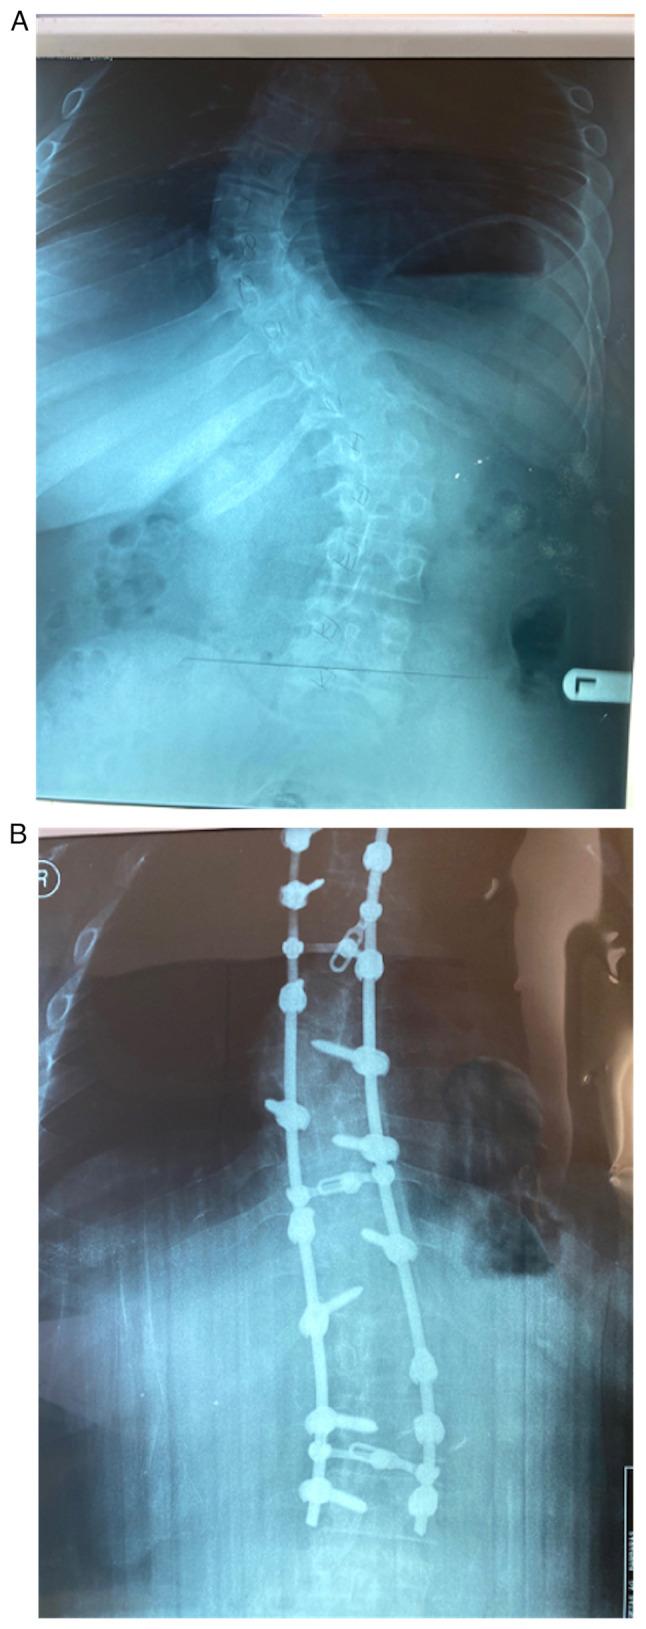

The aim of this case report is to present a rare case of acute slipped femoral capital on a chronic slipped capital femoral epiphysis (SCFE) after spinal fusion due to idiopathic scoliosis. A 14 year old male patient underwent posterior spinal fusion due to idiopathic thoracic scoliosis. Post-operatively, the patient presented with acute pain in the left hip and a reduced range of motion, which revealed acute SCFE. The patient was then referred to the Second Orthopaedic Department of Agia Sofia Children Hospital in Athens, and underwent percutaneous pinning of the left femur, after which he was discharged uneventfully. The follow up was excellent with no impact on the patient's daily life. The case described is extremely rare in the current literature. The significance of the pre-operative planning is underlined by this case, as well as the need for the spinal surgeon to be aware of the possibility of acute pain in the hip in young adolescents, as SCFE is more common amongst this demographic.

本病例报告的目的是呈现一例罕见的因特发性脊柱侧弯行脊柱融合术后,慢性股骨头骨骺滑脱(SCFE)基础上发生急性股骨头骨骺滑脱的病例。一名14岁男性患者因特发性胸椎侧弯接受了后路脊柱融合术。术后,患者出现左髋部急性疼痛且活动范围减小,检查发现急性SCFE。随后患者被转诊至雅典阿吉亚索菲亚儿童医院第二骨科,接受了左股骨经皮穿针固定术,术后顺利出院。随访情况良好,对患者日常生活无影响。目前文献中描述的该病例极为罕见。此病例强调了术前规划的重要性,以及脊柱外科医生需要意识到青少年髋部急性疼痛的可能性,因为SCFE在这一人群中更为常见。